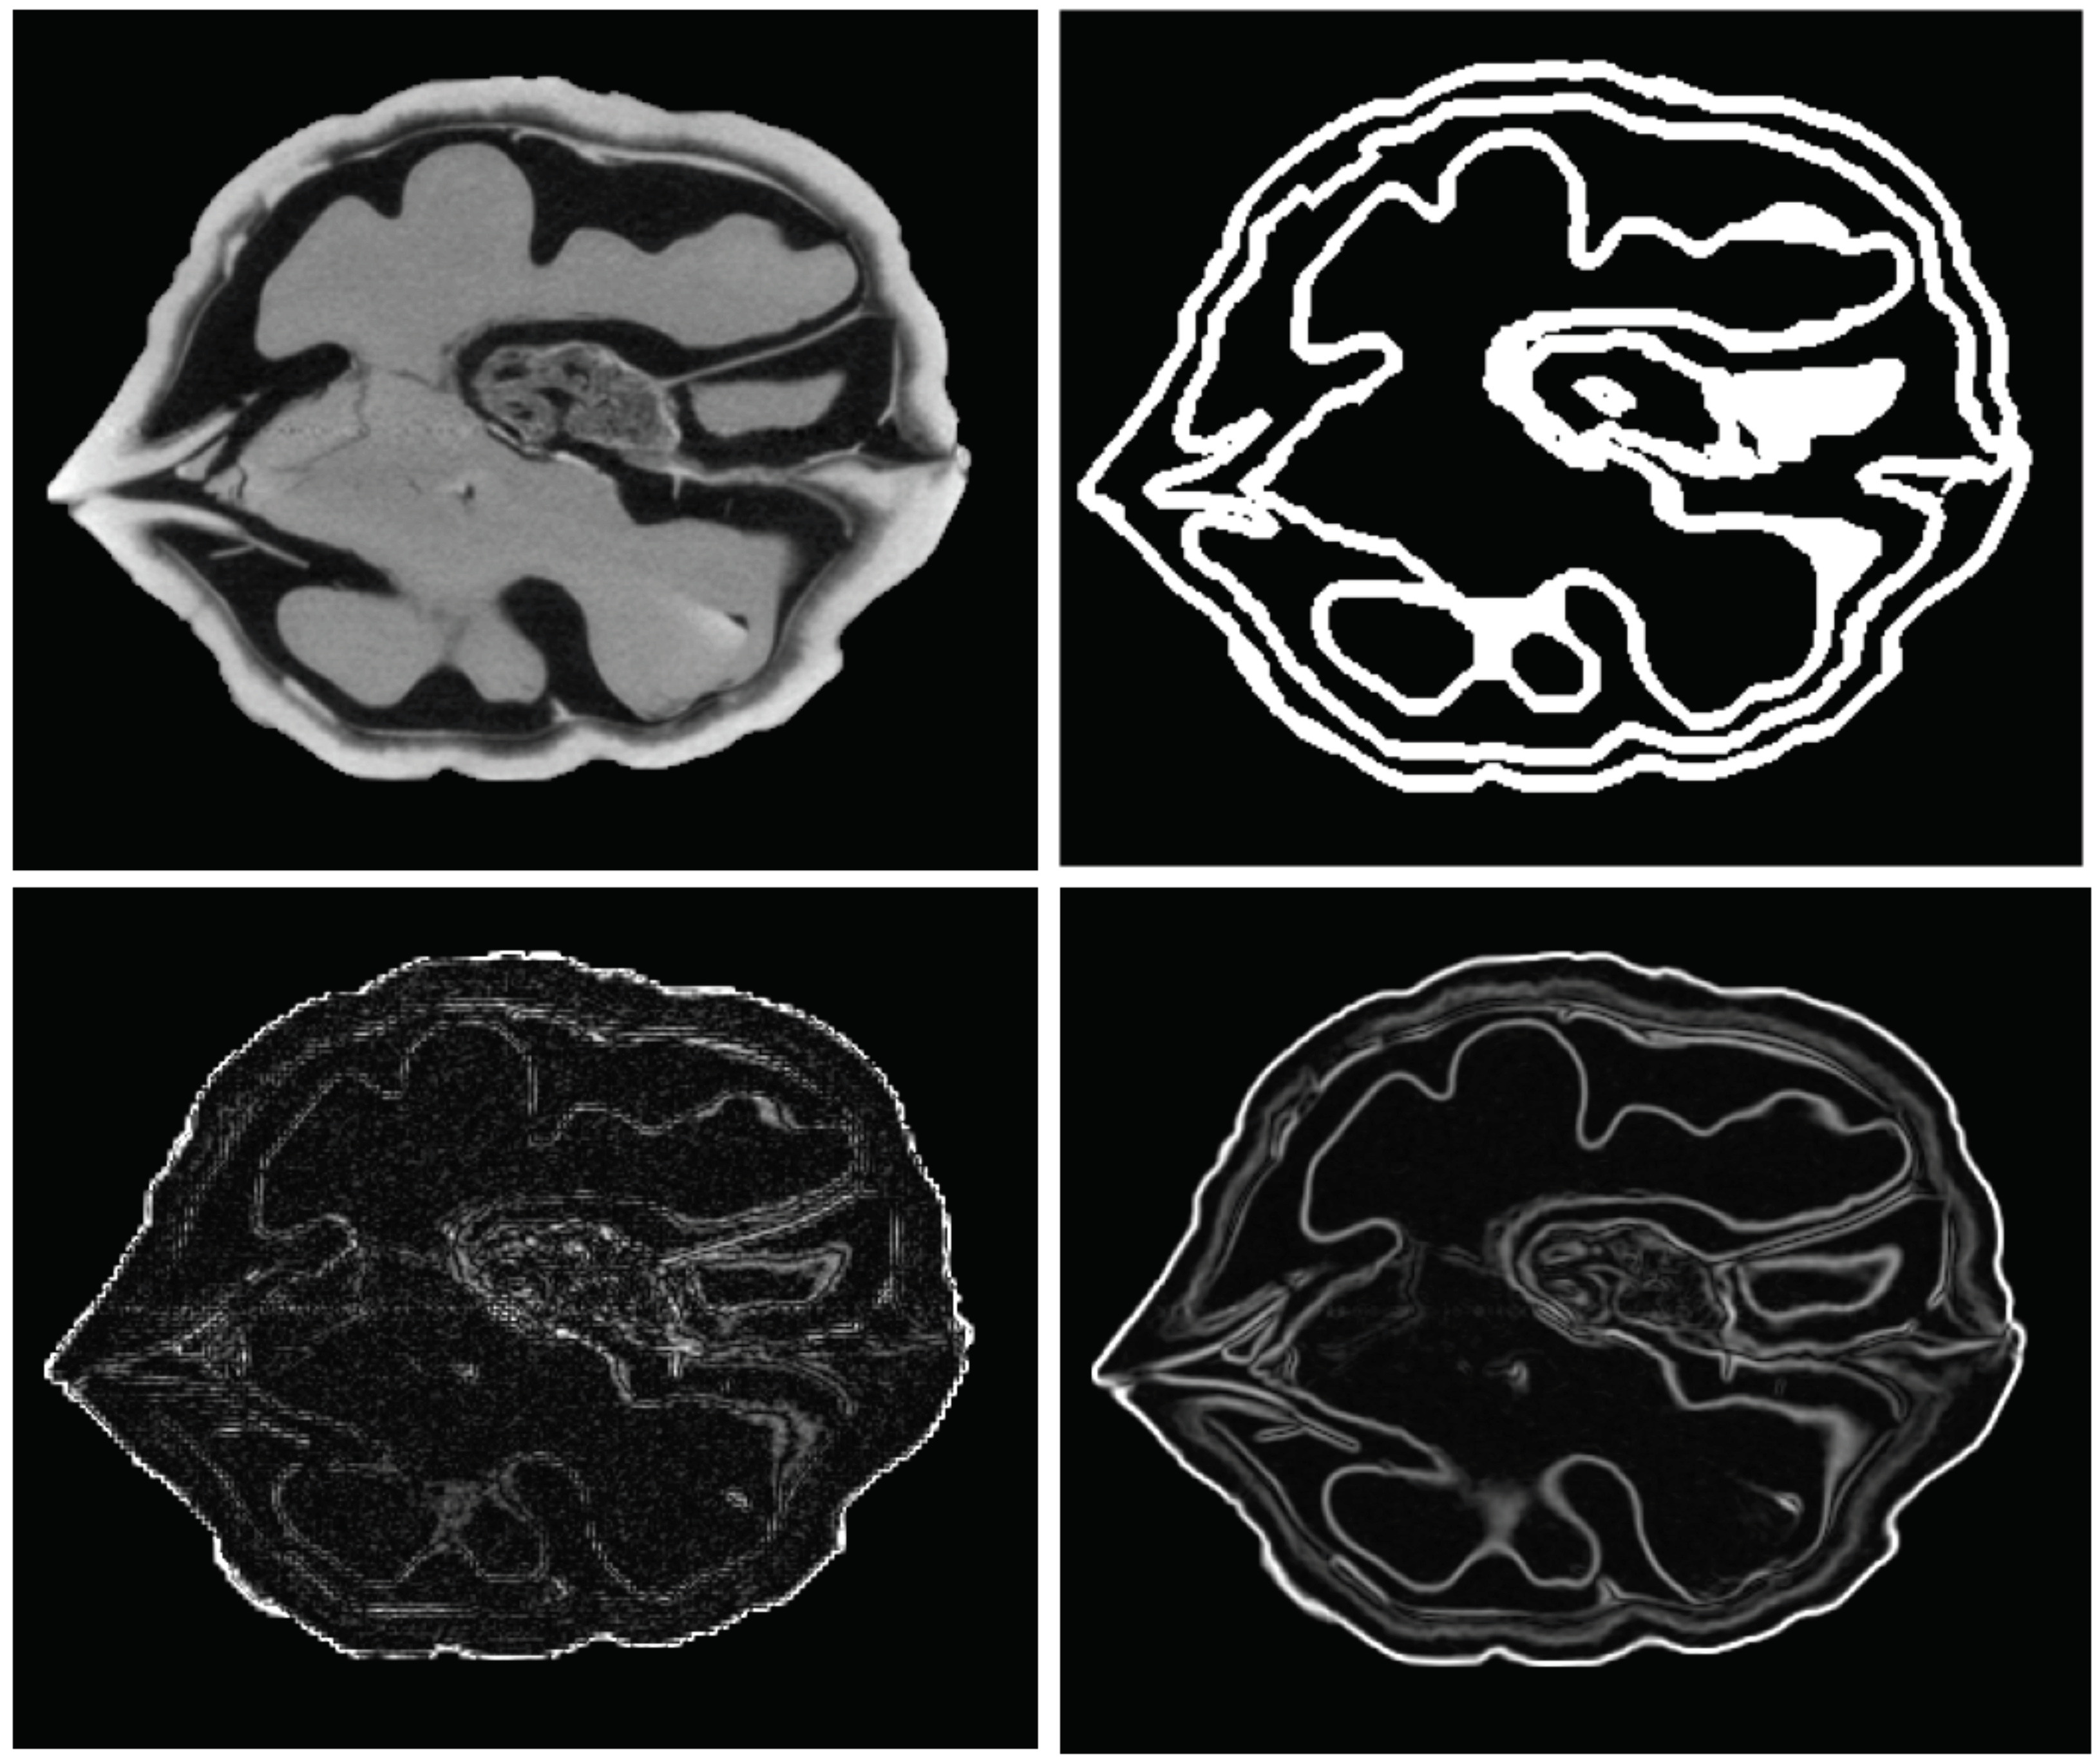

- A 3D isotropic MRI, T1-weighted of one of the authors’ heads. Skull-stripping and automatical segmentation was conducted with GIF [28]. Size: ;